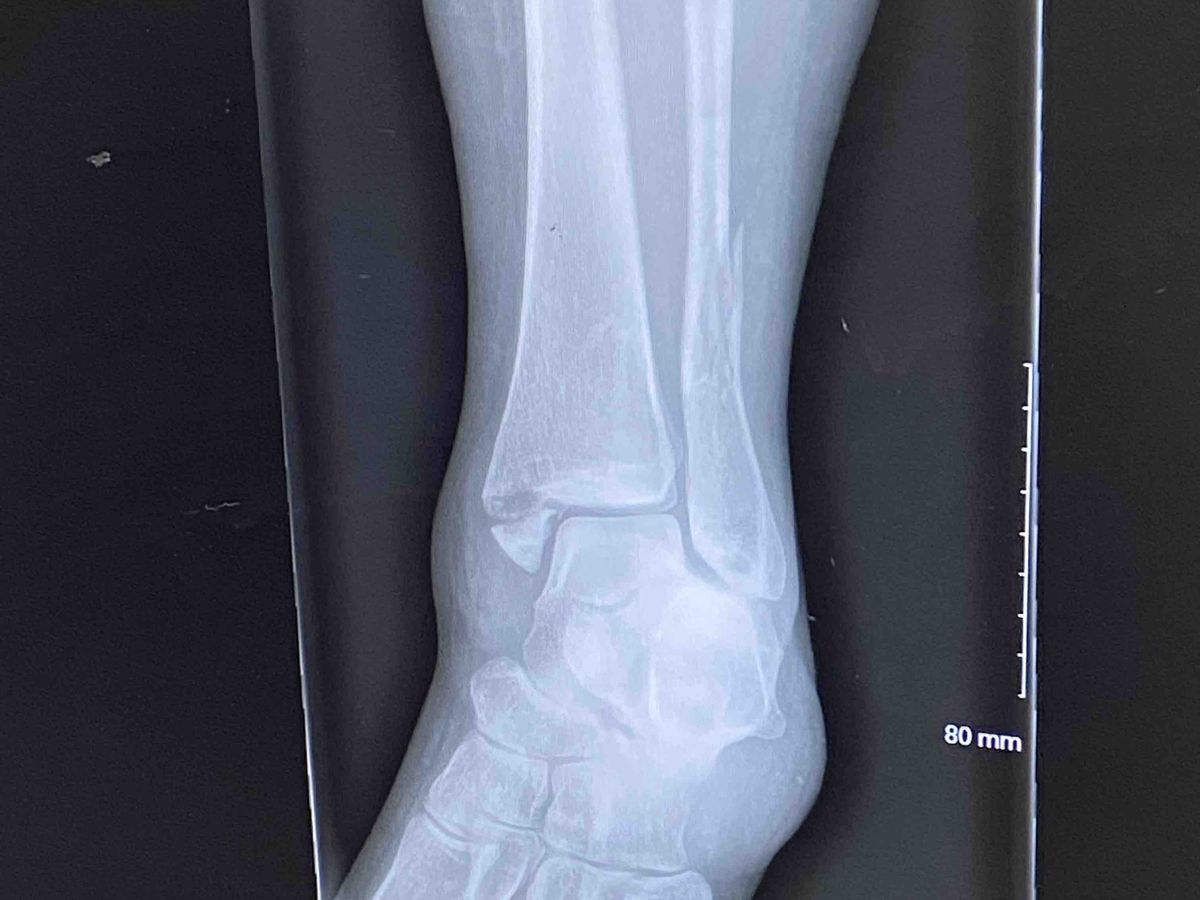

She had a rough landing which resulted in four fractures of her left ankle involving the fibula, tibia, and syndesmosis joint. Without an emergent ORIF surgery (open reduction and internal fixation) involving plates and screws to stabilize her ankle, the bones will heal incorrectly and she would be left with constant pain in the ankle/leg.